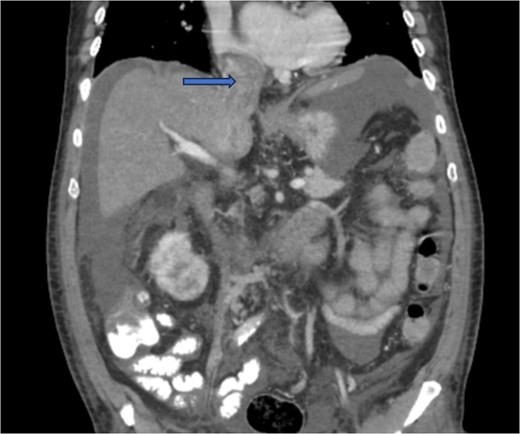

Diagnostic imaging began with a chest X-ray that indicated bilateral pleural effusions. An abdominal ultrasound detected a 4.6 × 4.2 × 4.3 cm echogenic lesion in the right hepatic lobe. Further imaging with a computed tomography (CT) scan of the chest, abdomen, and pelvis revealed a large mass originating from the posterior aspect of the right mid-kidney consistent with RCC (Fig. 1). The mass associated with thrombus extended into the renal sinus and collecting system, traveled along the right renal vein to the inferior vena cava (IVC), and projected into the right atrium (Figs 2 and 3). During hospitalization, bilateral lower extremity pain led to the diagnosis of bilateral deep vein thromboses via duplex venous ultrasound. Echocardiography showed normal left ventricular ejection fraction, impaired diastolic filling, mildly increased ventricular wall thickness, and an echogenic mass extending from the right atrium into the IVC consistent with the tumor thrombus.

CT chest abdomen and pelvis with contrast showing inferior extension to the level of the distal margin of the IVC.